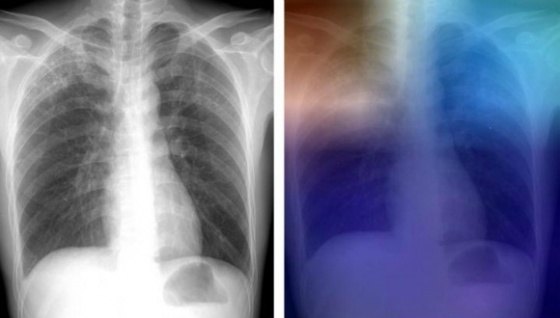

Yapay zekanın tıp alanındaki uygulamalarıyla, daha doğru hastalık teşhisleri yapılabilecek. Araştırmacılar tüberküloz teşhisi için yeni bir yapay zeka teknolojisi geliştiriyor.

Philadelphia'daki Thomas Jefferson Üniversitesi Hastanesi'nden araştırmacıların çalışması sayesinde yapay zekanın tıp alanına uygulanarak radyoloji uzmanına gerek kalmadan radyografi görüntü yorumlamaları yapılabilir.

Yapılan testlerde olgular, TB-pozitif ve TB-negatif X-ışınlarından öğrenilen iki farklı DCNN modelini (AlexNet ve GoogLeNet) test etmek için kullanıldı. Modellerin doğruluğu, 150 vaka üzerinde test edildi. En iyi performans gösteren yapay zeka modeli AlexNet ve GoogLeNet'in birleşmesi oldu. Bu modelin net doğruluk yüzde 96’ya ulaştı.

Yapay zeka çözümü

İki DCNN modeli, 150 test davasından 13'ünde ortak karar veremedi. Bu vakalar için araştırmacılar, uzman bir radyoloğun görüntüleri yorumlayabildiği ve vakaların yüzde 100'ünün doğru teşhis edildiği bir iş akışını değerlendirdi. Bir insanı döngüye dahil eden bu iş akışı yüzde 99'a yakın net doğruluk oranına ulaştı.

Geliştirme çalışmaları ve yeterli sayıda testlerin yapılması ile göğüs görüntüleme Teknolojilerini kullanan bir yapay zeka çözümü, tüberküloz ile mücadelede büyük rol oynayabilir.